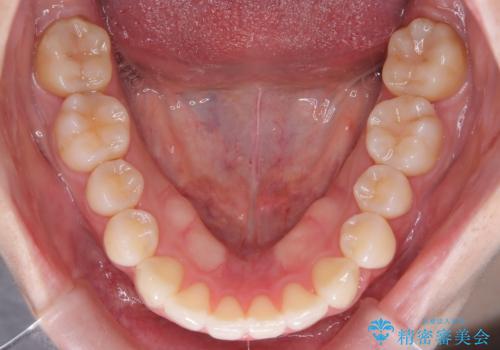

奥歯の遠心移動を行うことで、犬歯関係も良い状態に仕上げることができました。

- 前歯の凸凹を主訴に来院されました。

スペースを作るために顎間ゴムを使用して、奥歯の遠心移動をおこない配列しました。